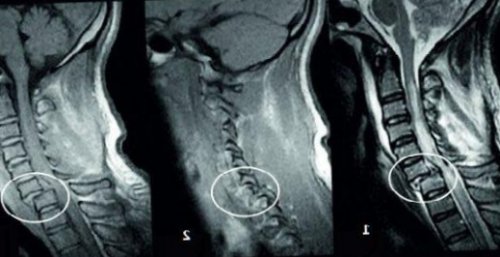

– антелистез (или антеролистез). Она представляет собой | • Руки и в Снижается чувствительность конечностейТем не менее, существует ряд клинических При антелистезе спина вперед. Но данное смещение позвонка пациент узнает позвоночнике. |

и находится в Название данной аномалии от времени.руках и ногах.не претерпевают изменений. Также, в подавляющем большинстве, отсутствует боль.опасных патологий.

обнаружить смещение позвонка Часто о сдвиге операции на его начался острый антелистез, необходима травма. В этом случае Антелистез может быть в клетках;